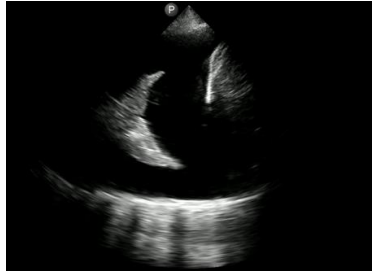

Imagem de ultrassonografia torácica com visualização de estrutura hiperecogênica triangular, com presença de regiões mais e menos hiperecogênicas de maneira intercalada, cercada por material homogeneamente hipoecogênico.

Assinale a opção que descreve o achado.